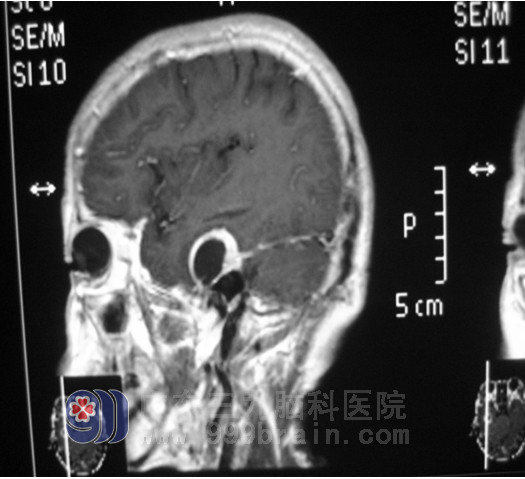

广东三九脑科医院神经外五科医生为卢阿姨完善了相关检查,颅脑MRI(磁共振)+增强示:右颞底部囊实性占位。初步诊断:1.右颞叶占位;2.高血压病(3级 极高危)。经神经外五科鲁明 主任了解,原来卢阿姨原有右侧中耳乳突炎症病史,结合其临床表现及影像学检查,鲁明 主任初步考虑卢阿姨患的可能系硬膜外脓肿。http://www.999brain.com/

入院后一周,卢阿姨接受了“右颞部硬膜外肿物切除术”。术中见肿物位于右颞中颅窝底,位于硬膜外,呈囊实性,内容物为淡绿色囊液,见实性部分呈灰白色、质软,显微镜下全切肿物,剥离病变包膜。http://www.999brain.com/

术前